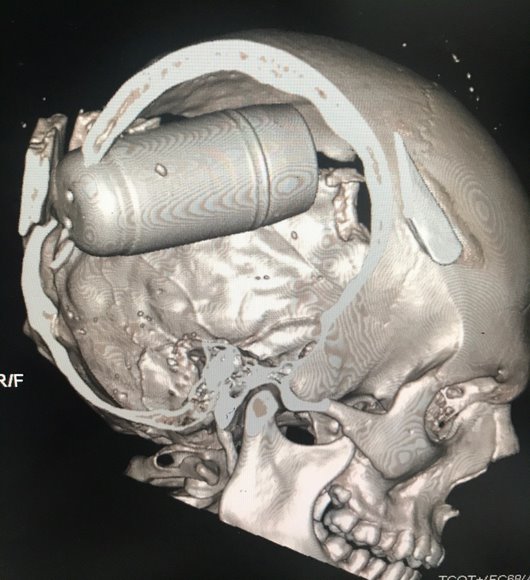

وتلقت منظمة العفو الدولية صور الأشعة المقطعية من عاملين في المجال الطبي في بغداد. وتؤكد الصور، التي تحققت منها منظمة العفو الدولية، الوفيات الناجمة عن ارتطام شديد بالرأس. والإصابات المروعة في كل هذه الصور ناتجة عن القنابل الكاملة المنغرسة في جماجم الضحايا.

وقالت لين معلوف، مديرة البحوث للشرق الأوسط في منظمة العفو الدولية: “تشير جميع الأدلة إلى قيام قوات الأمن العراقية باستخدام هذه القنابل العسكرية ضد المحتجين في بغداد، مستهدفة، على ما يبدو، رؤوسهم أو جسدهم من مسافة قريبة وبصورة مباشرة. وكان لهذا نتائج مدمرة، في حالات متعددة اخترقت جماجم الضحايا، مما أدى إلى جروح مروعة وموت بعد أن تنغرس القنابل داخل رؤوسهم “.

تشير جميع الأدلة إلى قيام قوات الأمن العراقية باستخدام هذه القنابل العسكرية ضد المحتجين في بغداد، مستهدفة، على ما يبدو، رؤوسهم أو جسدهم من مسافة قريبة وبصورة مباشرة. وكان لهذا نتائج مدمرة، في حالات متعددة اخترقت جماجم الضحايا، مما أدى إلى جروح مروعة وموت بعد أن تنغرس القنابل داخل رؤوسهم.

وأظهرت أشرطة الفيديو هذه خمسة رجال تعرضوا لإصابة حادة في الرأس بسبب القنابل على ما يبدو. ففي مقطع فيديو، تم تصويره في 25 أكتوبر/تشرين الأول، على الجانب الشمالي الشرقي لجسر الجمهورية، يمكن رؤية محتج فاقد الوعي أو توفي، مع جرح واضح في الجزء الخلفي من جمجمته ينبعث منه الدخان أو الغاز. ويمكن رؤية الآثار نفسها في مقطع فيديو آخر تم تصويره في نفس اليوم وفي نفس المكان – وهنا يوجد محتج آخر لديه جرح مماثل على يمين جمجمته. ويظهر مقطع فيديو آخر، تم تصويره في 25 أو 26 أكتوبر/تشرين الأول، مجموعة من المحتجين يمشون فوق جسر الجمهورية في اتجاه المنطقة الخضراء بالمدينة. وفجأة، يسقط أحد المحتجين على الأرض وهو ممسك برأسه، وسحب الدخان أو الغاز تنبعث من الجرح.

جميع الأسلحة الأقل فتكا يمكن أن تسبب القتل عندما تستخدم بشكل غير صحيح. ويجب عدم إطلاق عبوات الغاز المسيل للدموع مباشرة على الناس. ومع ذلك، فإن جميع الخبراء الذين قابلتهم منظمة العفو الدولية – من بينهم الخبراء العسكريون، والخبراء في أعمال الشرطة، والأطباء، وأخصائيو الطب الشرعي – يتفقون على أن عدد الوفيات والطبيعة المروعة للإصابات الناجمة عن إطلاق قذائف القنابل المسيلة للدموع الثقيلة، والتي يبلغ طولها 40 مم، من مسافة قريبة بصورة مباشرة أمر غير مسبوق. وأكد خبير الطب الشرعي لمنظمة العفو الدولية أنهم “لم يروا مثل هذه الإصابات الشديدة بسبب هذا من قبل”. وأشار الخبير إلى أن “شدة الإصابة وزوايا الاختراق” تشير بقوة إلى أن القنابل أطلقت مباشرة على الضحايا بدلاً من الارتداد عن الأرض.

فقد أفاد عامل طبي في مستشفى قريب من ساحة التحرير نُقل إليه معظم الضحايا وقد تلقوا إصابات حادة في الرأس، تحدث إلى منظمة العفو الدولية، بشرط عدم الكشف عن هويته أن المرفق قد تلقى “ست إلى سبع إصابات في الرأس يومياً منذ يوم الجمعة [25 أكتوبر/تشرين الأول]”. “من بين هؤلاء، خمسة كان لديهم مقذوفات أو عبوات منغرسة في جماجمهم”. وقال العامل الطبي أنهم لم يروا مثل هذه الإصابات بهذا الشكل المتكرر من قبل.